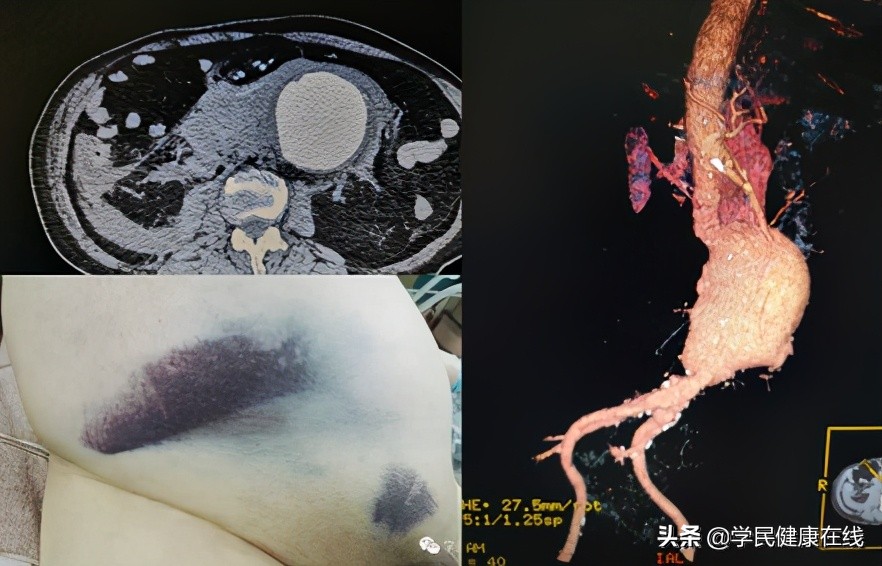

图1.破裂的腹主动脉瘤

腹主动脉瘤是一种困扰老年社会的血管外科疾病,其发病隐匿,经常直到破裂前才出现症状,主要是腹部或腰背部的疼痛,可以伴有昏厥,而一旦破裂许多患者没有机会到达医院。历史上一些名人因此病而失去生命,最著名的有爱因斯坦、戴高乐和李四光。但在他们那个年代,血管外科还没有得到发展,人工血管也没有,当年爱因斯坦的主治医生,只能拿包裹糖果的玻璃纸包在动脉瘤外面。爱因斯坦很幸运,又生存了7年,其他人就没那么幸运了。

后来出现了手术置换腹主动脉的技术,但主动脉是人体内最粗的动脉,这么粗的血管出了问题,人体自身没有合适的替代材料,曾经有人用同种异体的主动脉作为置换材料,但无法满足临床需求,直到人工血管的出现,使这种手术得以推广。但开刀手术创伤较大,术中出血较多,恢复较慢。而且腹主动脉瘤经常破裂之前没有症状,一旦破裂后,即便到达医院,接受外科治疗,死亡率也高达80%。其手术需要医院有强大的综合能力,国内一般只有大医院有能力开展。